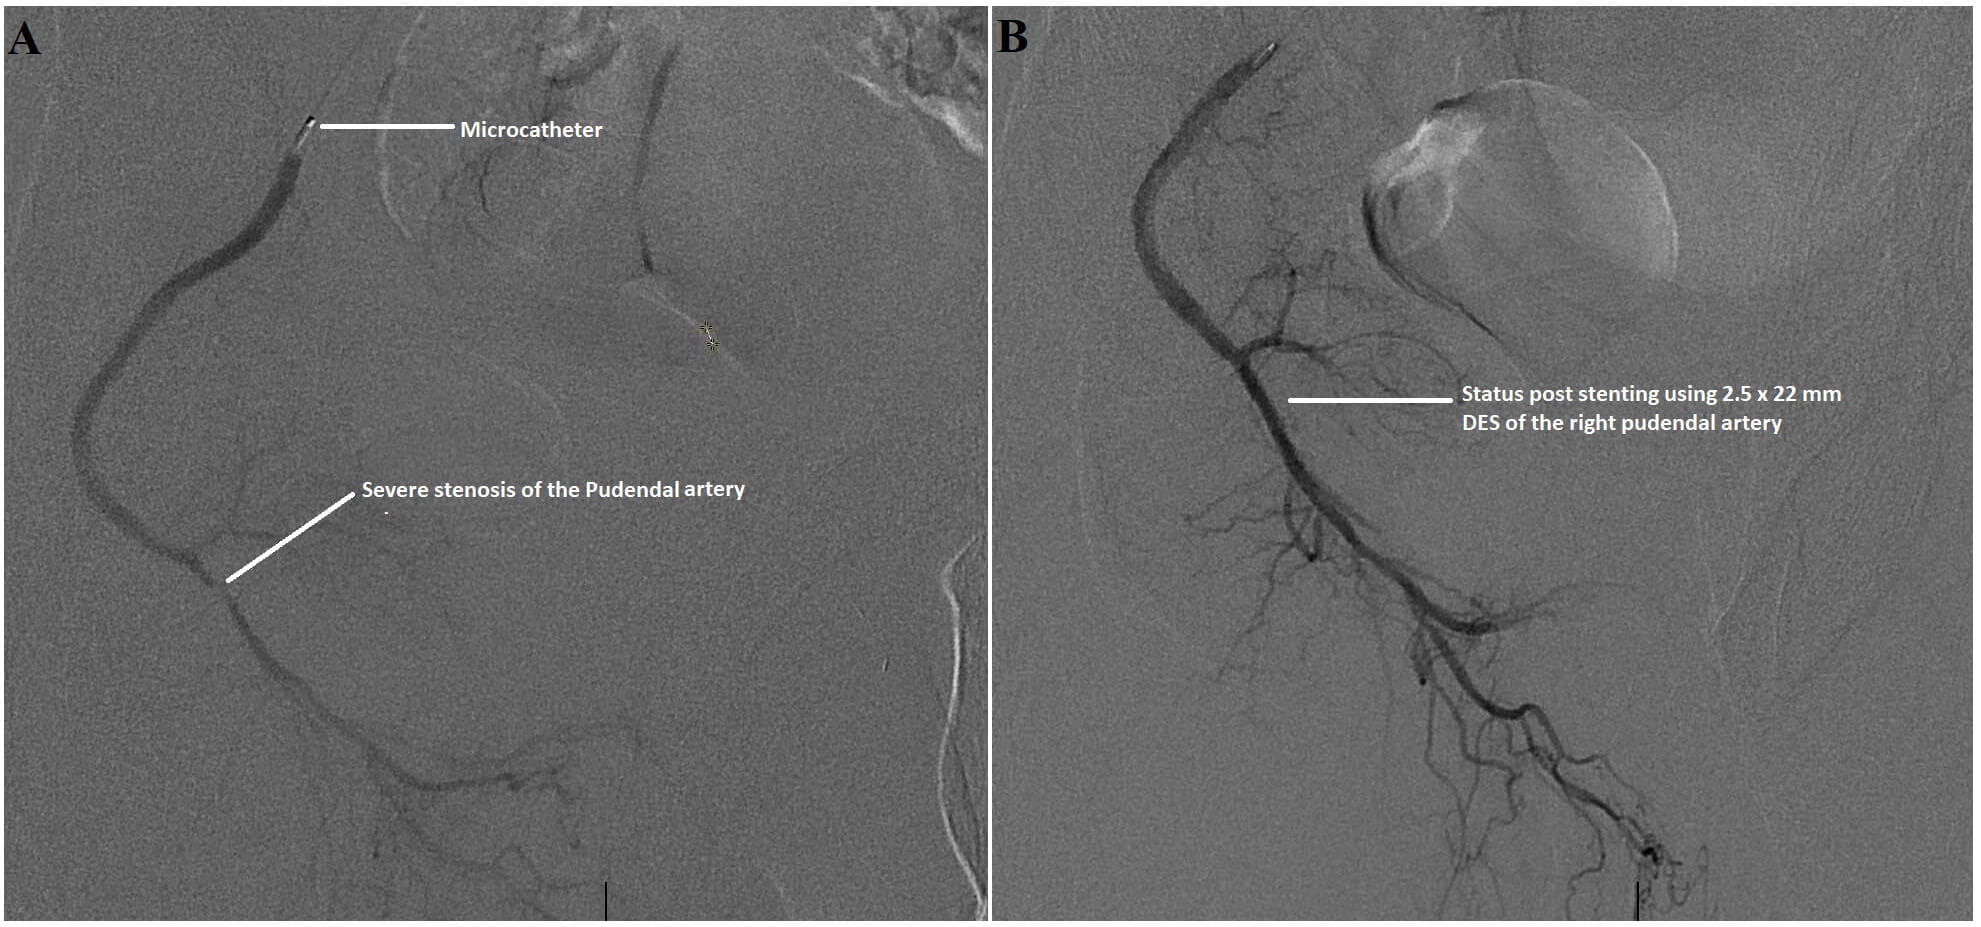

“In the past, we didn’t have a very good treatment for this,” Dr. Shishehbor says. “However, now we have better techniques. We have special wires and special balloons. The same way that we can get into the brain and fix a blockage in the brain, the same way that we can get into the heart and fix a blockage in the heart, we can now improve blood flow to the penis by performing angioplasty and stenting, removing and pushing to the side those blockages that are preventing the blood from getting to the penis. We have extensive experience with this procedure, and we have published a number of articles around the technical aspects, but it is not something that is widely done. Not every center offers this.”

Men undergoing the minimally invasive endovascular procedure for vasculogenic ED at University Hospitals Cleveland Medical Center are under conscious sedation. The entire procedure takes about an hour to 90 minutes.